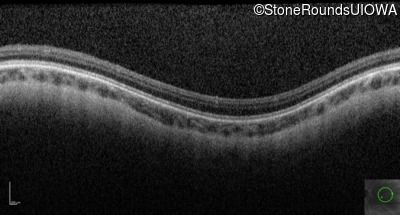

Optical Coherence Tomography - Left - 10/200 sc

Exemplar / OCT Stack